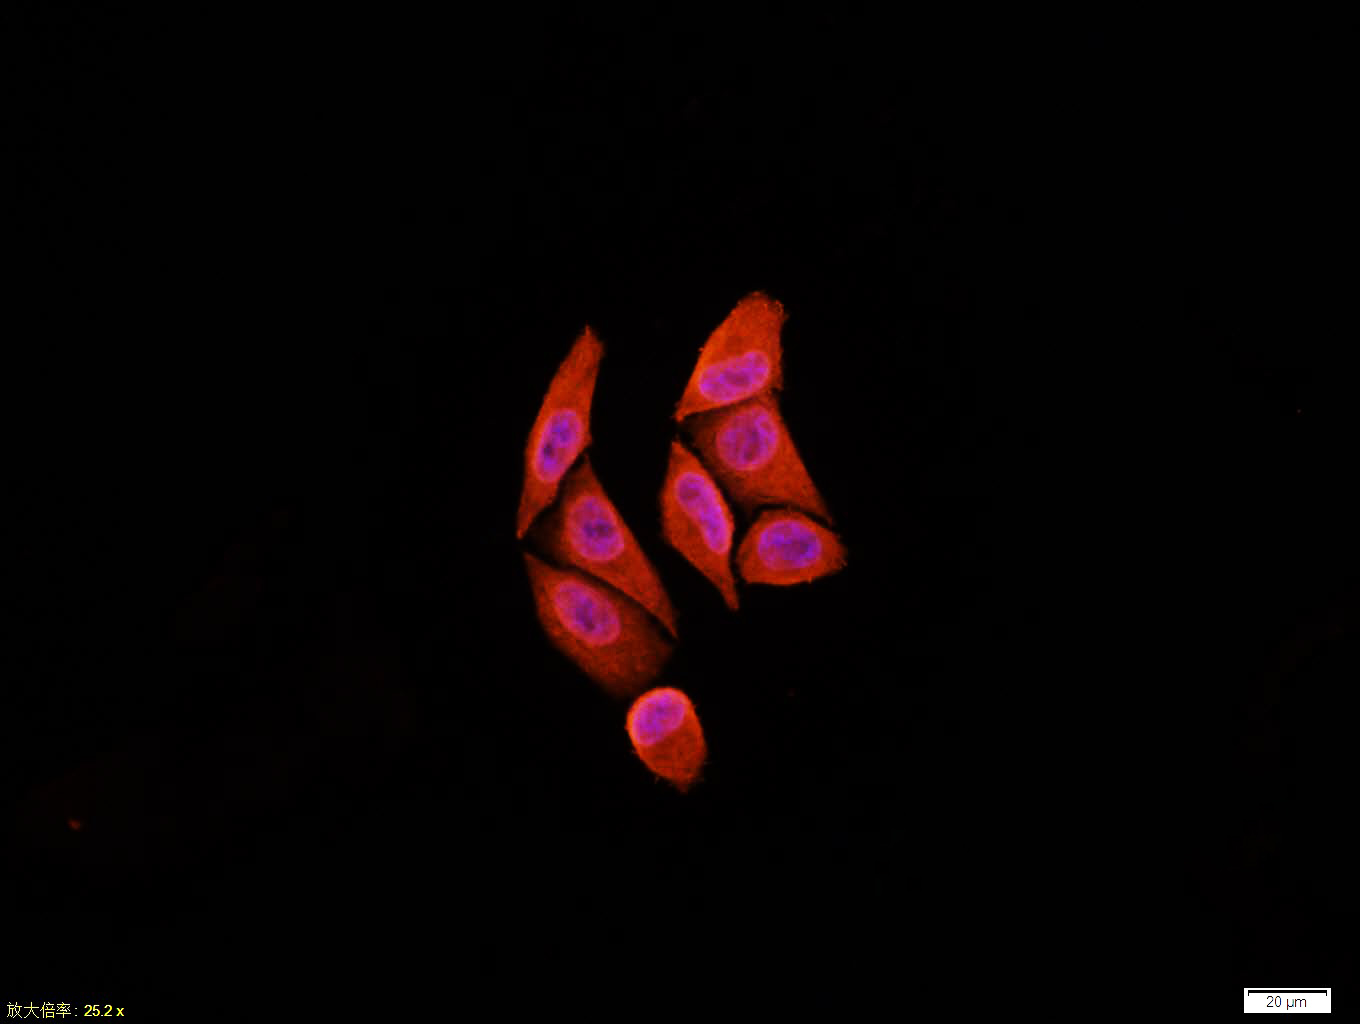

Tissue/cell:Hela cell; 4% Paraformaldehyde-fixed; Triton X-100 at room temperature for 20 min; Blocking buffer (normal goat serum,C-0005) at 37°C for 20 min; Antibody incubation with (EGFR) monoclonal Antibody, Unconjugated (bsm-33140M) 1:100, 90 minutes at 37°C; followed by a CY3 conjugated Goat Anti-Mouse IgG antibody at 37°C for 90 minutes, DAPI (blue, C02-04002) was used to stain the cell nuclei.